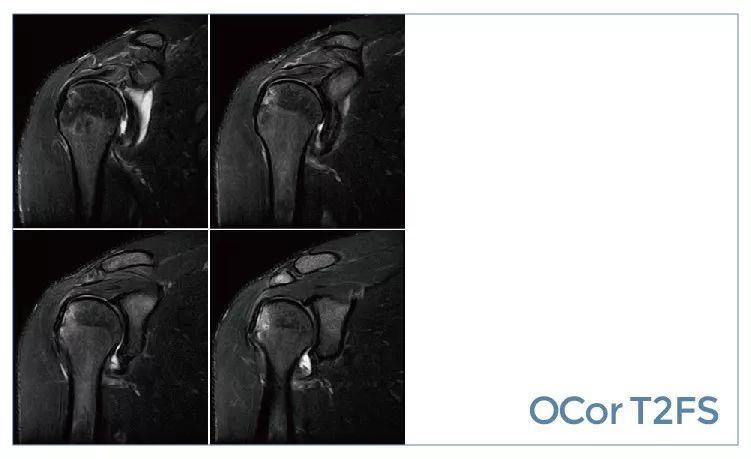

【朗润影像档案】磁共振影像病例分享(编号20190927)